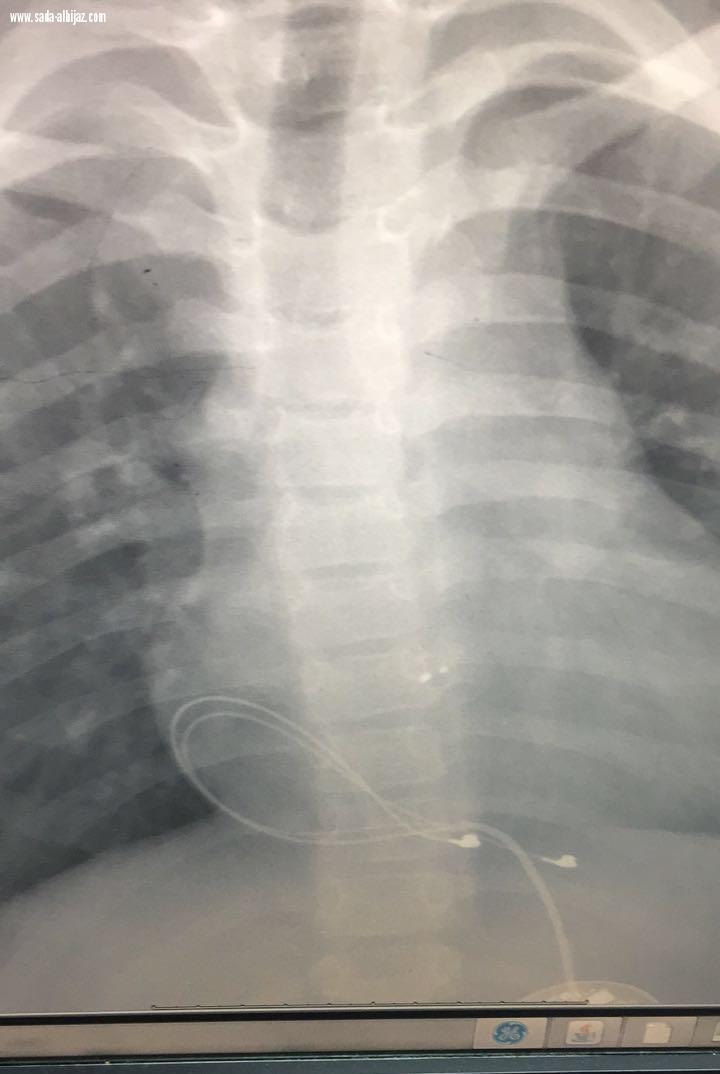

تمكن فريق طبي بمستشفى الولادة والأطفال بمكة المكرمة من إجراء جراحة ناجحة لإنقاذ حياة طفل أُصيب بتباطؤ شديد في ضربات القلب . وأوضح المدير الطبي بالمستشفى الدكتور هلال المالكي أن المستشفى إستقبلت إحالة طفل يبلغ من العمر 10 سنوات كحالة إنقاذ حياة حيث تباطئت ضربات القلب الى 30 في الدقيقة وعلى الفور تم إستدعاء فريق طبي متخصص بمركز قلب الأطفال من مستشفى الولادة والأطفال، بقيادة الدكتور خالد عطاس إستشاري قسطرة تشوهات القلب ورئيس مركز أم القرى للقلب مبيناً "ان الحالة تم الإطلاع على تقريرها المرفق من قبل المستشفى المحول منه وتبين أنه تم تركيب سدادة لإقفال ثقب بين البطينين وحصل له تباطؤ شديد في ضربات القلب بعد ذلك ، مما إستلزم تركيب منظم لضربات القلب

وبالكشف عليه من قبل المختصين من مركز القلب تبين خروج السلك الموصل بالقلب عن مكانه مع إمكانية وجود كسر فيه ، مما أثر سلبياً على ضربات القلب حيث تم التدخل السريع لإجراء عملية جراحية لإزالة السلك المكسور وزرع منظم جديد من قبل جراح قلب اطفال د محمد قنديل والاستشاريون المختصون في قلب الأطفال حيث تمكن جراحي القلب من السيطرة على الوضع بفضل من الله تعالى وعادت ضربات القلب لوضعها الطبيعي وحالة الطفل مستقرة بفضل من الله "